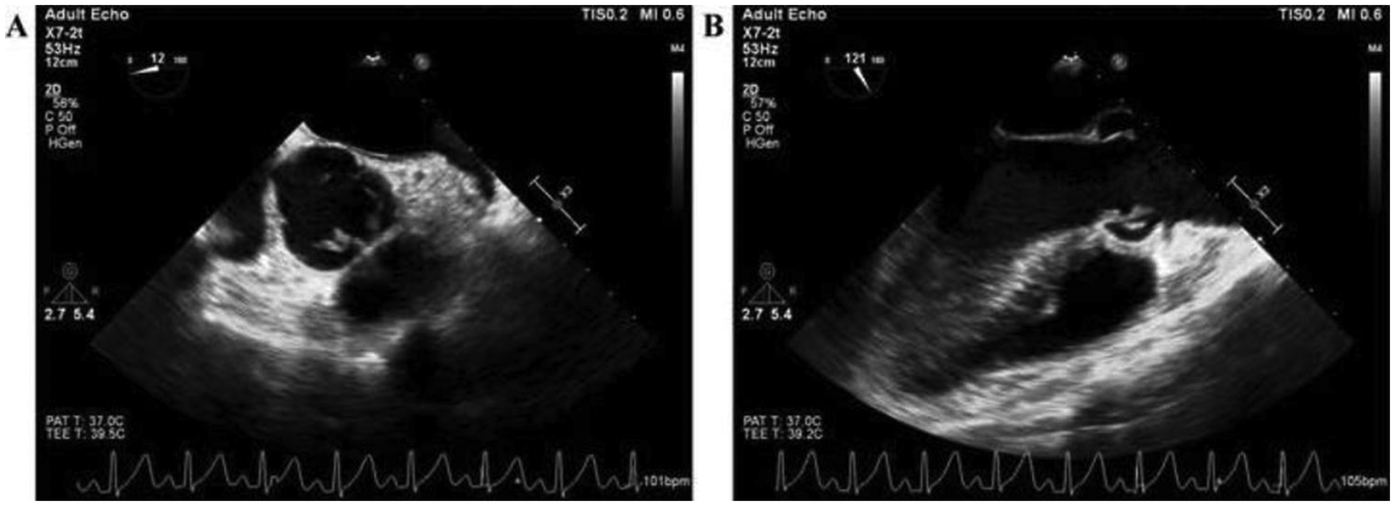

A 36-year-old male patient was admitted to the Department of Cardiovascular Surgery in our hospital on February 4, 2021, with a complaint of fever lasting for 4 days. The patient was diagnosed with rheumatic heart disease at another hospital more than 20 years prior to admission to our hospital. Color Doppler ultrasound showed emboli in the interphalangeal artery between the left index finger and middle finger, as well as in the dorsalis pedis artery. The results of the physical examination after admission were as follows: clear consciousness, T 39.4°C, P 115 beats/min, R 22 beats/min, and BP 115/84 mmHg. Breath sounds were clear on bilateral auscultation, and no dry or wet rales were heard. Heart rate was 115 beats per minute, paced heart rhythm and no murmur was heard in each valve auscultation area. The results of blood routine and PCT tests done on February 5 were: white blood cell 11.70 × 109/L, neutrophil count 9.12 × 109/L, lymphocyte count 1.61 × 109/L, erythrocyte count 3.72 × 1012/L, hemoglobin 99 g/L, platelets 305 × 109/L, and PCT 0.14 ng/ml. The results of coagulation screening were as follows: prothrombin time (PT) 17.0 s, international normalized ratio (INR) 1.54; Activated Partial Thromboplastin Time (APTT) 37.7 s, fibrinogen (FIB) 5.11 g/L, and D-dimer 0.63 mg/L. The results of complete set of biochemical testing done on February 5 were: total protein 62.3 g/L, albumin 28.9 g/L, total bilirubin 13.3 umol/L, alanine aminotransferase (ALT) 39 U/L, aspartate aminotransferase (AST) 28 U/L, glucose 4.96 mmol/L, blood urea nitrogen (BUN) 3.60 mmol/L, creatinine 72.0 umol/L, and plasma uric acid 154 umol/L. Autoantibodies for autoimmune hepatitis and TORCH screening were negative. Transesophageal echocardiography (TEE) showed that the right coronary valve had no coronary valve prolapse, multiple abnormal echogenicity (formation of vegetation), and severe aortic insufficiency (Figure 1).

Figure 1

The image of transesophageal echocardiography before anti-infective therapy.